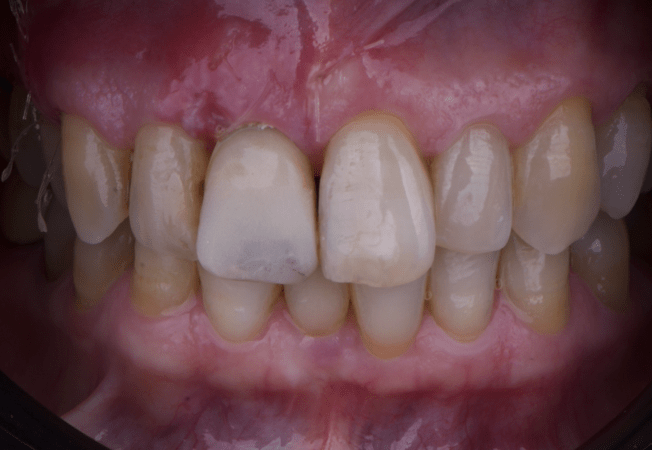

The provisional not only satisfied the patient’s functional and esthetic demands but also played a key role in shaping the emergence profile and conditioning the gingival margin. By providing a provisional solution immediately, the patient was able to leave the clinic with a natural-looking smile, avoiding any psychological or social impact associated with tooth loss in the anterior maxilla.

After an appropriate healing period, the definitive prosthesis was planned and delivered. A screw-retained zirconia crown was fabricated to ensure long-term durability, optimal esthetics, and retrievability. Zirconia was selected for its mechanical strength and excellent esthetic properties, blending seamlessly with the adjacent natural dentition in both form and color.

The final crown was designed to maintain the gingival architecture that had been shaped by the provisional. Special attention was paid to the emergence profile, contact points, and translucency to achieve harmony with the patient’s smile. The definitive restoration provided functional stability and esthetic integration, fulfilling the patient’s expectations for a fixed and natural solution.